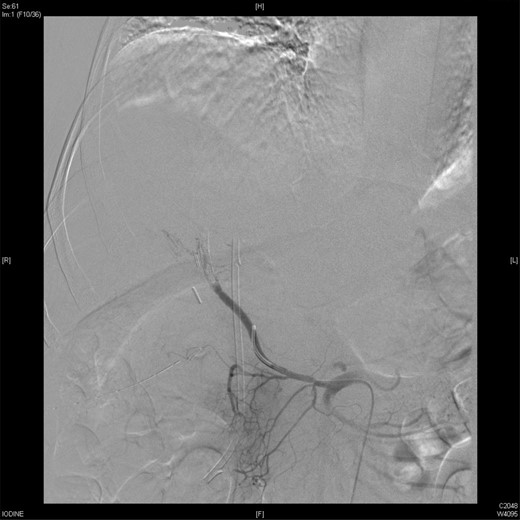

On Day 7, the patient bled again from the same aneurysm of the left hepatic artery. A repeated angiography revealed the bleeding with a reduced flow in the stented, replaced right hepatic artery (Fig. 4). The active bleeding was stopped using gel-foam embolization of the two branches of the left hepatic artery (Fig. 5) with a decision to embolize the whole left hepatic artery if bleeding did not stop while holding the heparin infusion. The patient's liver function was preserved, and the bleeding stopped despite anticoagulation.

An angiographic scan showed reduced flow in the stented replaced right hepatic artery.